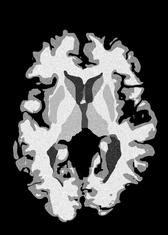

4.2 Registration to a 100 micron ex-vivo brain MRI volume

To showcase the efficacy of our method on real large scale images, we register a 250 in-vivo MRI image (Lüsebrink et al., 2017) to a 100 ex-vivo FLASH human brain volume (Edlow et al., 2019). This represents an inverse problem with more than 11.2B optimizable parameters (compared to 20M for clinical datasets), or 44.8GB of GPU memory. The entire problem does not fit on most GPUs, necessitating distributed multimodal registration. We optimize a composite transform - affine followed by a diffeomorphic mapping; details can be found in Section E.1. Multimodal deformable registration took 58 seconds on 8 NVIDIA A6000 GPUs, which is unprecedented at this resolution. Fig. 6 shows qualitative results, highlighting the ability to register highly detailed structures such as cerebellar white matter; these structures are not visible at macroscopic scales. The resultant advantages of performing registration at this scale can allow researchers to characterize the neuroanatomy at microscopic resolutions and allow morphometric analysis of cortical layers and subcortical nuclei among other structures.